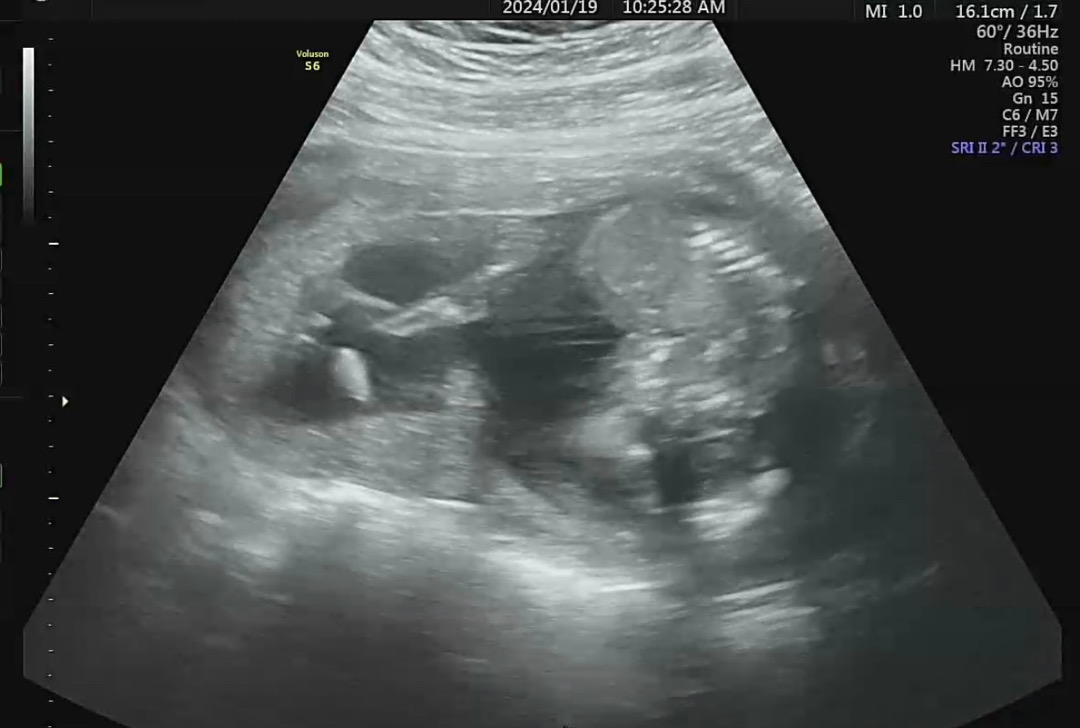

15주6일 2차기형아 검사하고왔어요

아크로바틱 중인 아기..ㅎㅎ 양수가 많이 모자라는건 아닌데 좀 작다보니 선생님이 애기가 구겨져서 있네요 해서 놀랬어요 ㅠ ㅋㅋ 물론 저희가 보기에만 불편한자세 이지만 아기는 괜찮다 하더라구요 저렇게 되있어서 겨우겨우 보고왔네요 완전 정밀하겐 못본듯해서 아쉬워영 ㅠㅠ 성별도 일단 가랑이사이에 암것도 안보인다 하시긴 했는데 자세가 저러다 보니 ㅋㅋ 확실한지는 모르겠네요 ㅠㅠ 하루에 일리터 먹는데 더먹으라하니 완전..후우.. 그래도 내가 할 수 있는 유일한 일이니 먹어야겠어요!